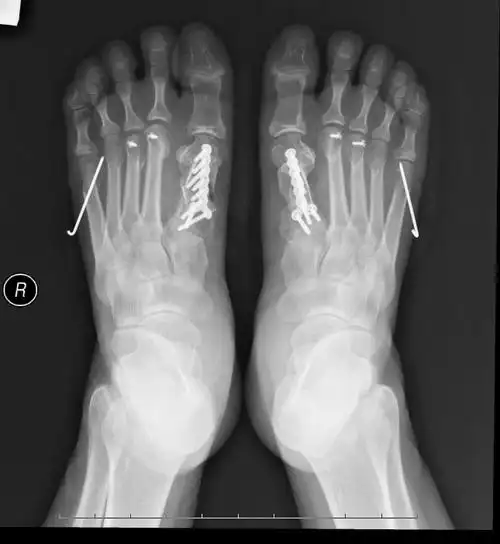

治疗后10月治疗后局麻下手术,创伤小,恢复快.

治疗中比较典型的e1型短趾症,夏天不敢穿凉鞋,冬天穿鞋脚趾头磨脚.